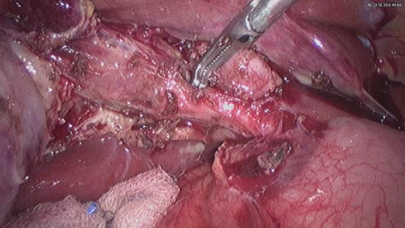

ภาพแสดงลักษณะต่างๆ ของการผ่าตัดถุงน้ำดี จะพบว่ามีความยากง่ายของการผ่าตัดแตกต่างกัน

ภาพการผ่าตัดผ่านกล้องถุงน้ำดีที่ยังไม่อักเสบ

ภาพการผ่าตัดผ่านกล้องถุงน้ำดีอักเสบ

ภาพการผ่าตัดผ่านกล้อง ถุงน้ำดีอักเสบ มีเนื้อตายที่ผิว

ภาพการผ่าตัดผ่านกล้อง ถุงน้ำดีอักเสบเป็นหนอง

จะพบได้ว่ามีความยาก-ง่ายในการผ่าตัดต่างกัน